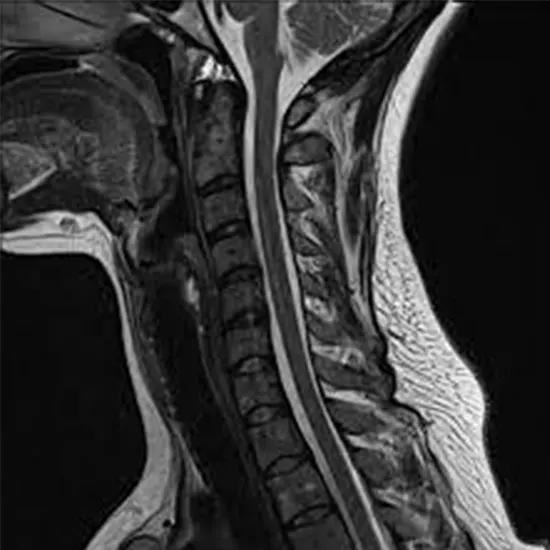

Cervical Spine MRI : This is the most common type of neck MRI and focuses on imaging the bony structures of the cervical spine (neck). It provides detailed images of the vertebral bodies, intervertebral discs, spinal cord, nerve roots, and surrounding soft tissues. Cervical spine MRI is useful for evaluating conditions such as herniated discs, spinal stenosis, spinal tumors, fractures, and spinal cord abnormalities.